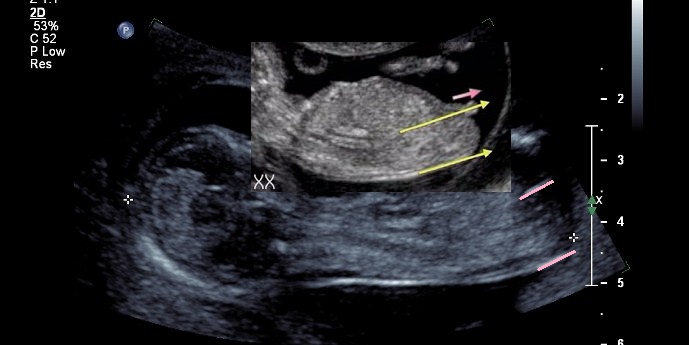

Ok so im still obsessing of my nub pic , so i drew lines to show the nubs angle with spine , im not sure if this is right but if the lower spine was more parallel than how my bubs is laying would that make the nub more parallel also , i know i know, im grasping at straws right ?

Attachment 1893